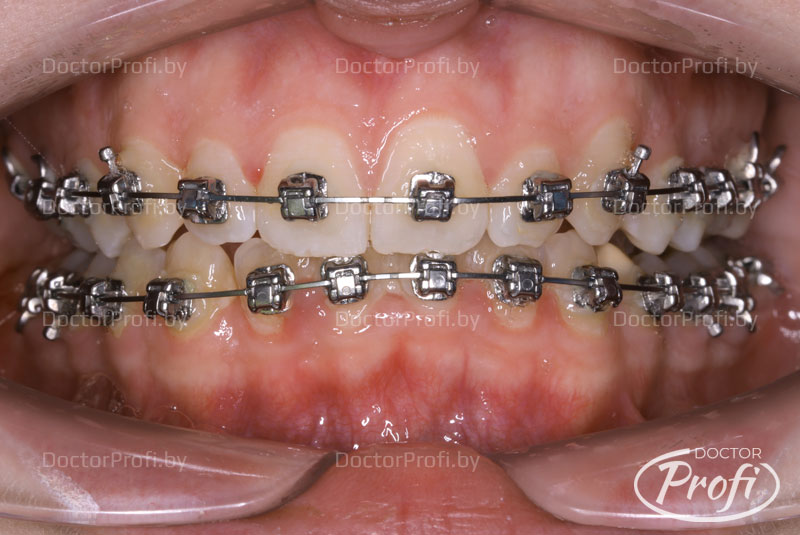

- Проведена коррекция прикуса без дополнительного удаления зубов.

- Улучшена форма зубных рядов и положение зубов.

- Ортодонтическое лечение проводилось брекет-системой Damon Q.

Срок лечения составил 16 месяцев. В результате проведенного лечения пациентка обрела красивую улыбку, правильный прикус, ровные и здоровые зубы.

После